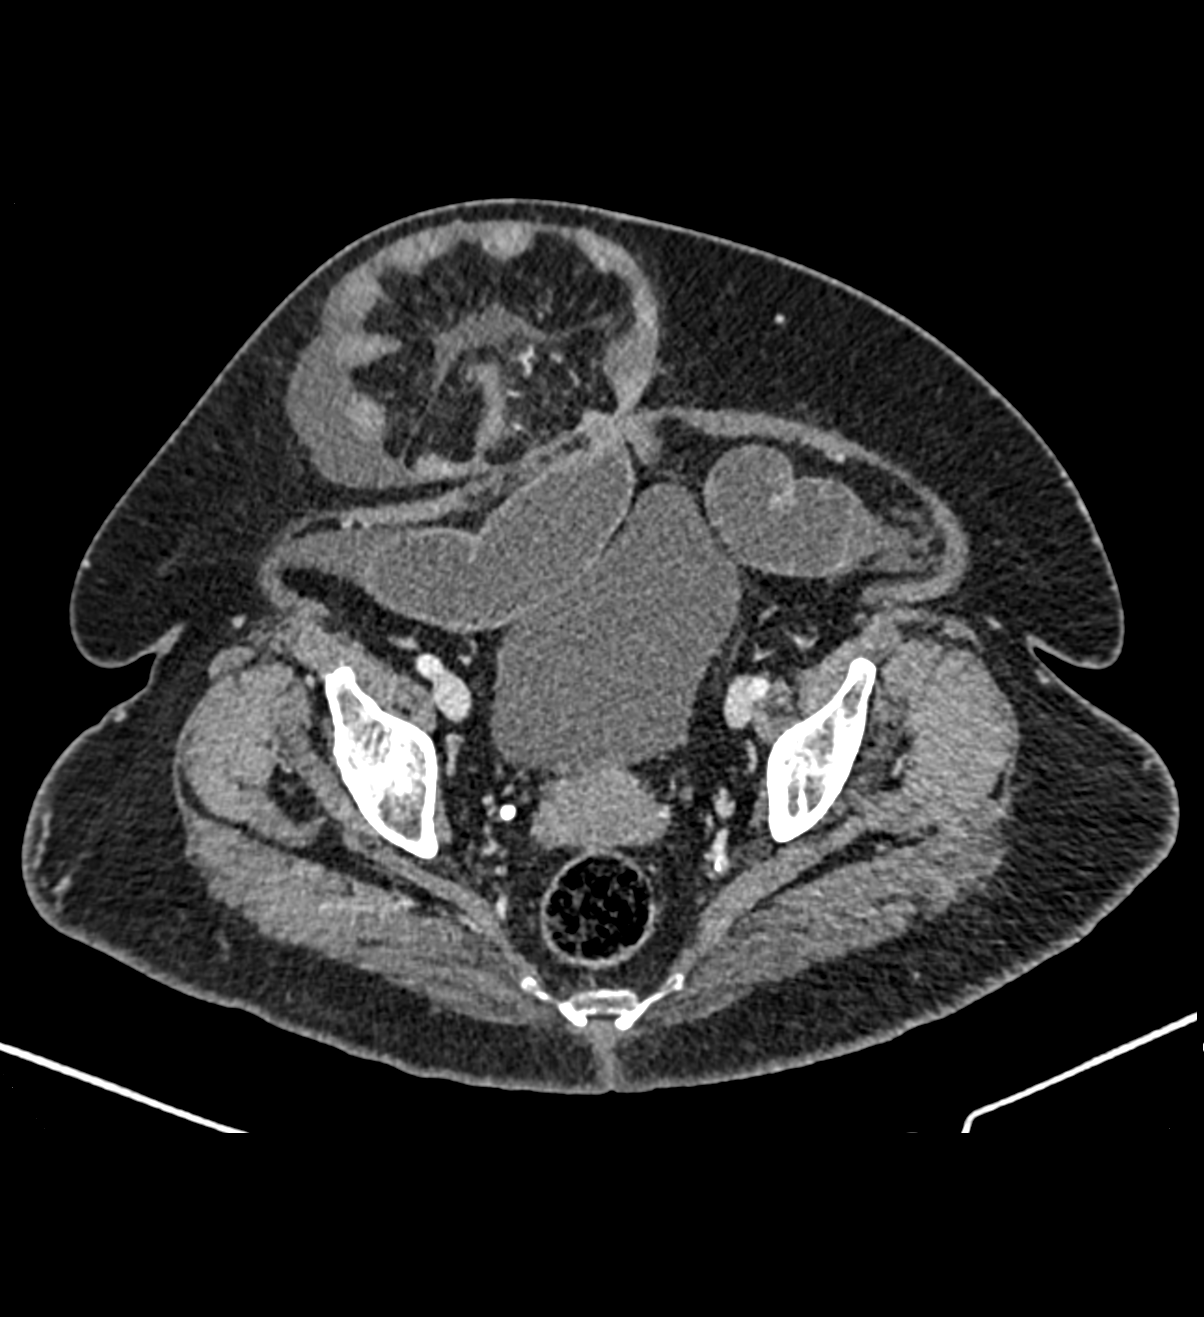

HALLAZGOS RADIOLÓGICOS